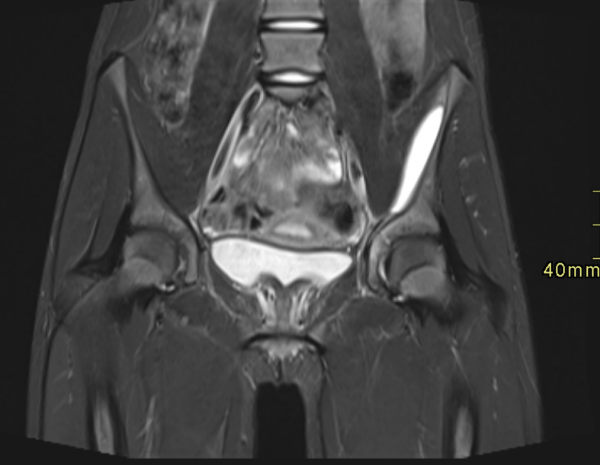

Secuencia de pelvis coronal, T2 STIR (Imagen 3). Se observa una imagen lentiforme subperióstica ilíaca izquierda de alta señal, bien delimitada, con un margen medial hipointenso. Leve asimetría de los huesos ilíacos, por mayor señal del izquierdo.